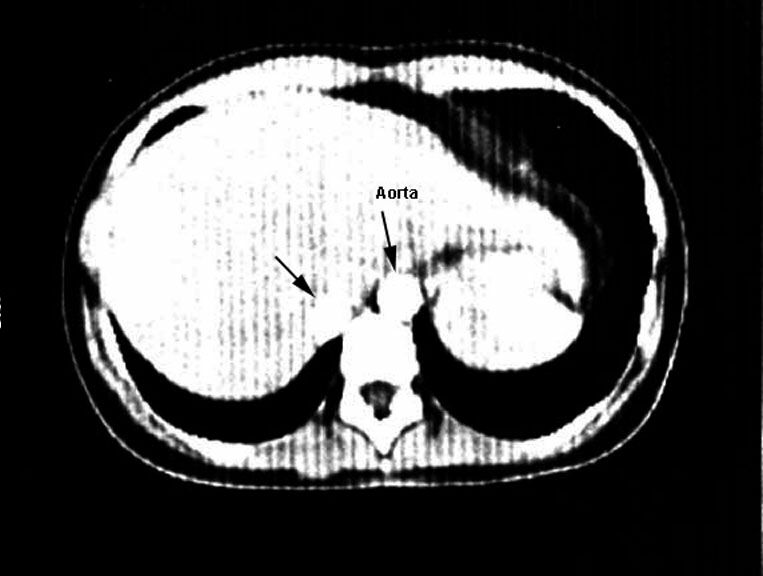

Anomalous artery and aorta

Increased blood flow to right lung base